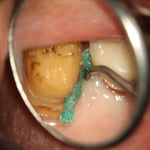

他院では抜歯と診断された歯ですが、それも間違えではありません。しかし、歯肉圧排をしたりすれば、保存できる可能性があることも多くあります。最初の状態ではラバーダム施すことが困難です。虫歯を除去中に歯髄の一部が露出しましたが、隔壁を作製し、防湿ができる環境を作って、歯髄を除去せずに保存できました。

クラウンを外すと、歯肉縁下までの大きな虫歯が確認できます。ラバーダムができないので、簡易防湿を行い、歯肉溝からの浸出液の侵入を防ぎます。隣の歯の間にまたがる虫歯ですが、丁寧に軟化象牙質を除去します。歯髄の露出はありましたが、特殊なセメントで緊密にシール(絆創膏みたいなもの)します。歯髄を除去せずにすみました。